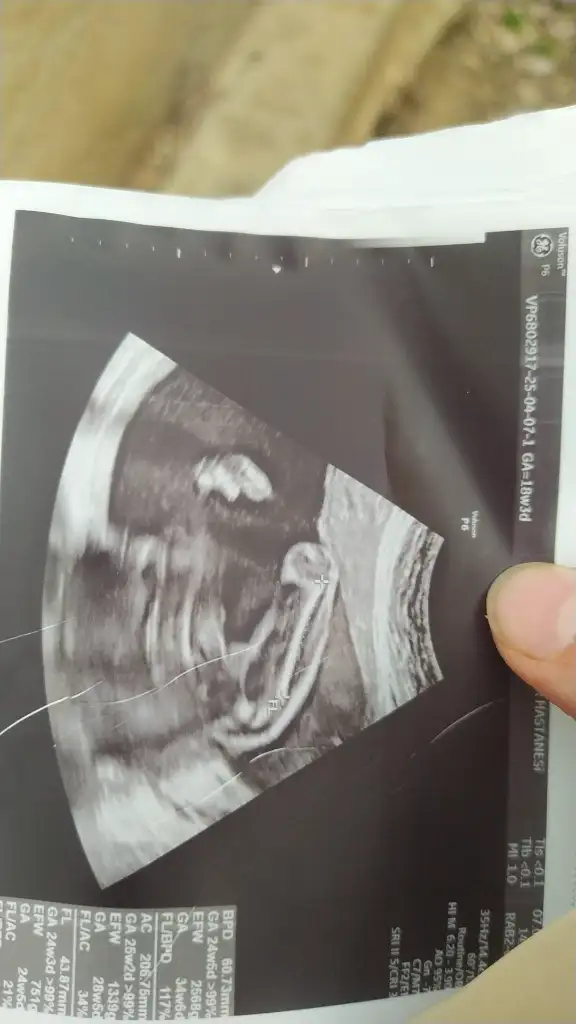

Kızlar 12 haftalık gebeyim. Nub teorisine göre cinsiyet tahmini yapabilir misiniz? İlk bebeğimiz ve biz cinsiyeti çok merak ediyoruz

• IMG_5708.webp

28 KB · Görüntüleme: 798